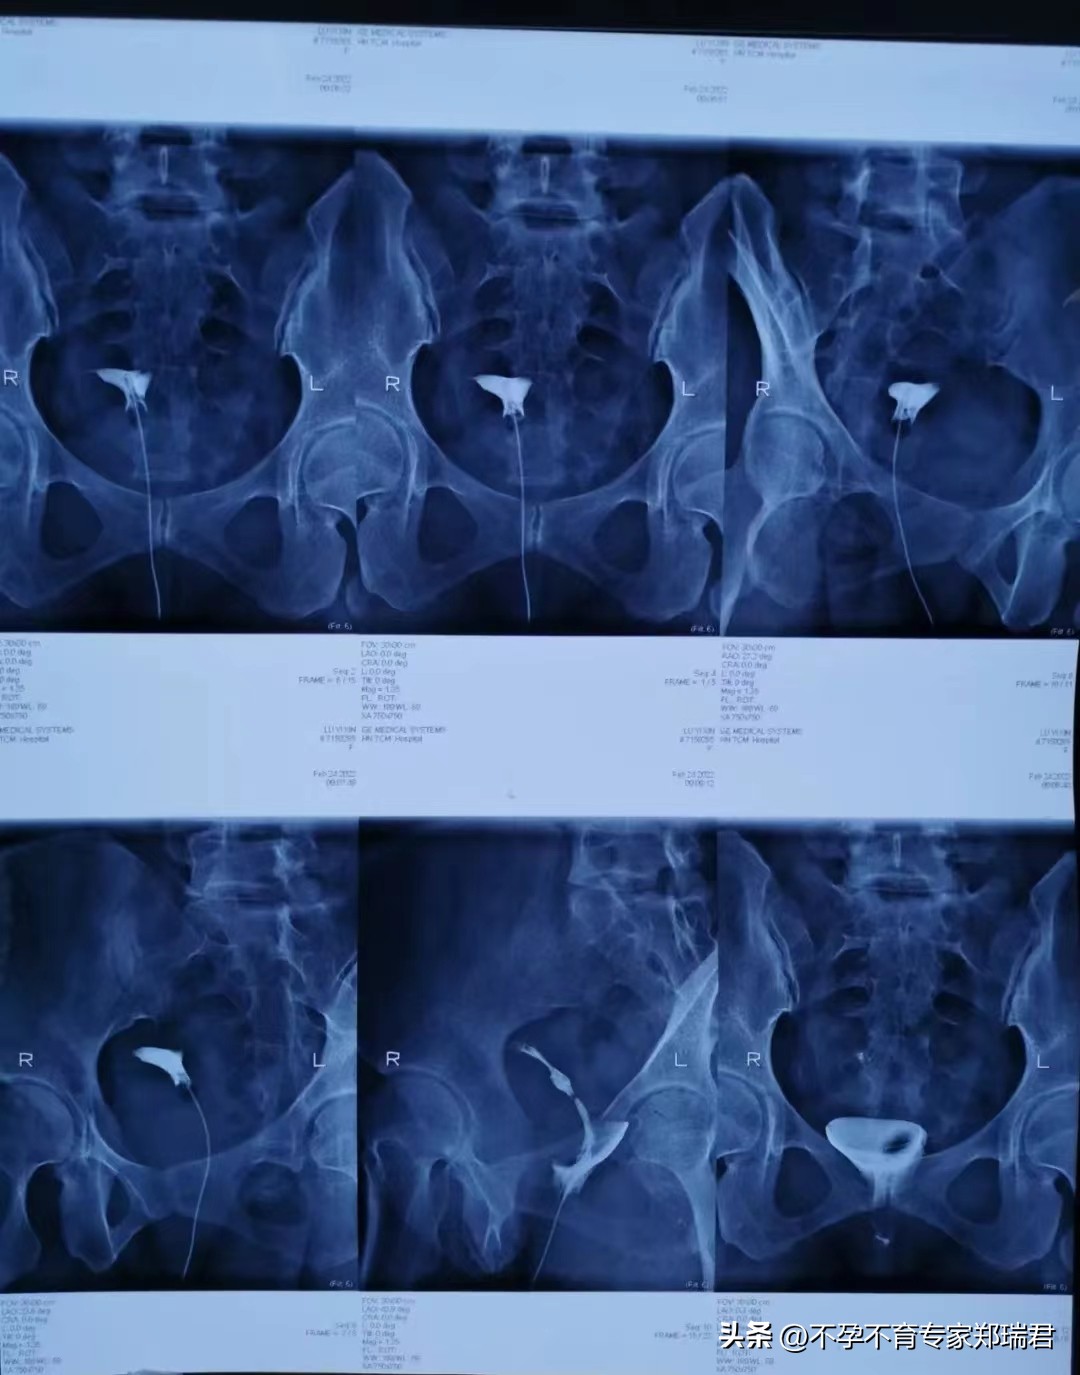

2022年2月24日子宫输卵管造影检查结果回示:

双侧输卵管不通!!

具体为:

宫体右偏;

右侧输卵管峡部近端显影梗阻;

左宫角轻度充盈缺损,左侧输卵管间质部梗阻。